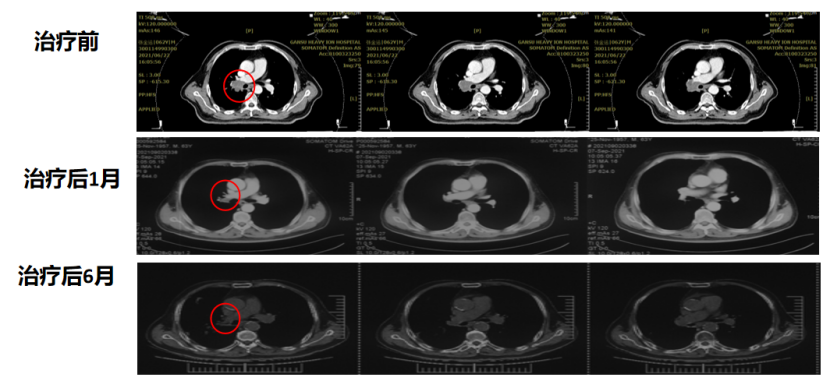

病例一:张xx,男,63岁,右肺小细胞肺癌,T2bN2M0,IIIA期 。重(碳)离子治疗后48个月,随访至今,状况良好。

病例三:王某某,女,69岁,新疆昌吉。诊断:1. 左肺恶性肿瘤 小细胞癌 cT3N2M1b IVA期(广泛期)KPS评分:90分;2. 肝转移癌。患者于2023-08体检发现左肺上叶软组织团块,肝左叶内下段转移结节;2023-10-31穿刺活检证实小细胞癌,Ki-67(80%+)。2023-12-20至2024-01-16患者于我院接受重(碳)离子放射治疗;于2023-12-25至2023-12-27接受肝脏转移灶的重(碳)离子放射治疗;同时接受预防性脑照射治疗;于2023-12-14至2023-12-17及2024-01-04至2024-01-07接受2周期EP方案同步化疗。截至2026年3月16日患者状况良好。

病例四:李某某,女,68岁,安徽省蚌埠市,诊断:1.左肺恶性肿瘤,小细胞神经内分泌癌,cT2N1M0 IIB期,KPS评分:90分;2. 冠脉狭窄。2024年1月因胸痛行CT冠脉造影发现左下肺门占位,约3.3cm。气管镜下取检,病检:小细胞神经内分泌癌,Ki-67(+,约90%)。诊断后行3周期依托泊苷、卡铂化疗。2024年3月在我中心接受了重(碳)离子治疗。截至2026年3月16日,重(碳)离子治疗后24个月,随访至今,状况良好。